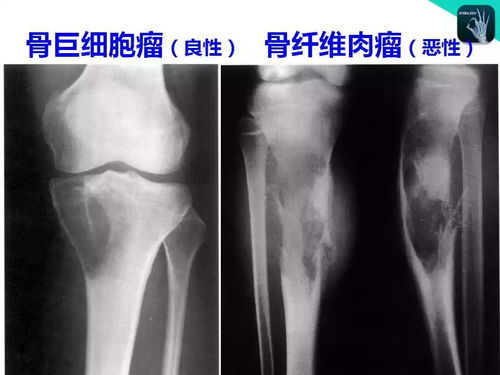

解析:在诊断骨肿瘤时,MRI具有较高的诊断价值。MRI可以清晰地显示肿瘤的形态、大小、边界以及与周围组织的关系,有助于判断肿瘤的性质和分期。此外,MRI还可以观察到肿瘤对周围血管、神经等结构的侵犯情况,为临床治疗提供重要依据。